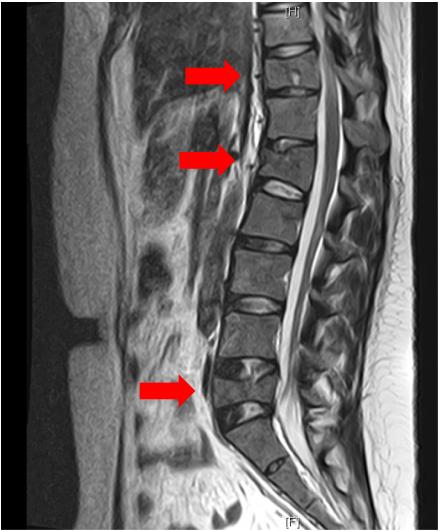

然而,患者的腰痛在产后5个月后仍持续存在。在一家骨科诊所接受了镇痛药的保守治疗。分娩后7个月,腰痛急剧恶化,因此换了另一家骨科诊所。患者没有经历过创伤。脊柱X线和MRI检查排除脊柱病变。在Th11、L1和L5处观察到多处压缩骨折(图1)。患者被送往医院接受进一步检查。

图1. 胸腰椎MRI T2图像。Th11、L1和L5多处压缩性骨折(箭头)